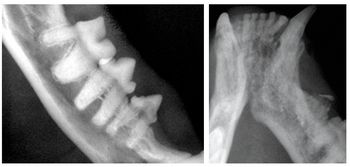

Radiographs produced without distortion are of great use in dentistry and are far easier to interpret than those with superimposed, foreshortened or elongated images.

Dr. Niemiec illustrates how to obtain dental radiographs using the correct bisecting angle.

Dr. Niemiec demonstrates the right positioning for obtaining dental radiographs of the maxillary canines.

Dr. Niemiec demonstrates how to avoid errors of vertical angulation when taking dental radiographs.